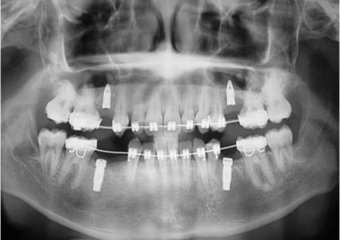

Raio x inicial, com agenesia de dentes permanentes